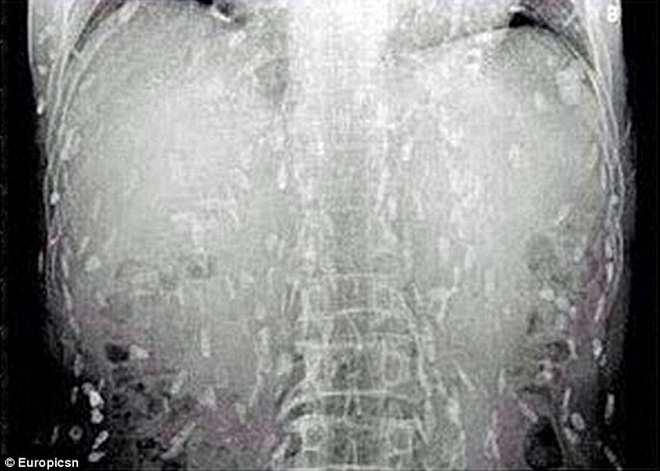

Những con sán làm tổ kín trên cơ thể người đàn ông.

Kết quả chụp X-quang tại Bệnh viện Nhân dân Quảng Châu 8, tại tỉnh Quảng Đông cho thấy, toàn bộ cơ thể người đàn ông đã bị nhiễm sán. Chúng nằm rải rác khắp nơi trên tay, chân, lưng, ngực cũng như bụng của anh.

Bác sĩ cho rằng, có thể cá và thịt sống mà người đàn ông ăn đã bị nhiễm sán. Trứng sán sau khi đi vào cơ thể đi theo đường máu để phát triển và sinh sôi. Được biết, loại sán này có thể gây nguy hiểm tới tính mạng người bệnh vì nó có thể xâm nhập vào não bộ.